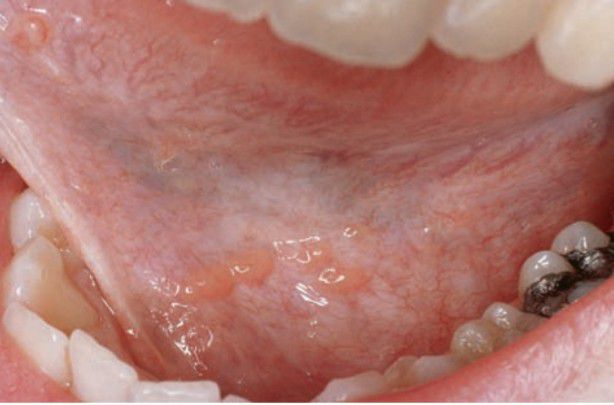

Ectopic lymphoid tissue in floor of mouth

Asymptomatic elevated yellow nodules ,0.5 cm in diameter; usually found on tonsillar pillars, posterolateral tongue, and floor of mouth; covered by intact epithelium.